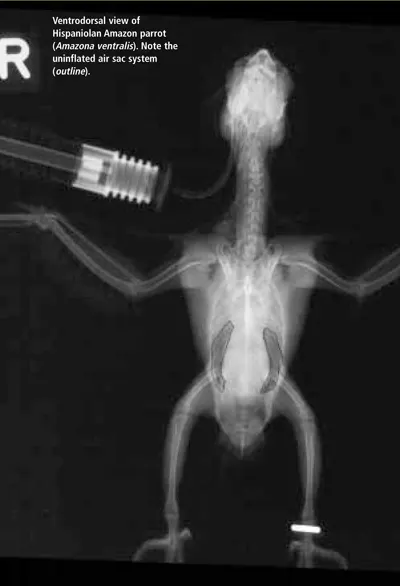

The avian respiratory system is extensive and complex. Becoming familiar with the normal presentation of respiratory anatomy through use of different imaging techniques will enhance a clinician's ability to make a diagnosis. This is the first of two articles using radiographic images and computed tomography (CT) to compare normal respiratory structures of the avian respiratory system. Note that the size of the patient dictates the size of the CT image. In this case, the patient is very small; thus, the images have become somewhat blurry with enlarging. Nevertheless, contrast is an important factor in CT imaging and the structures are quite clear. This article focuses on the body; the next part will address the head. For larger images, please click on the PDF icon at the top of the page to download the print version of the article in its entirety.